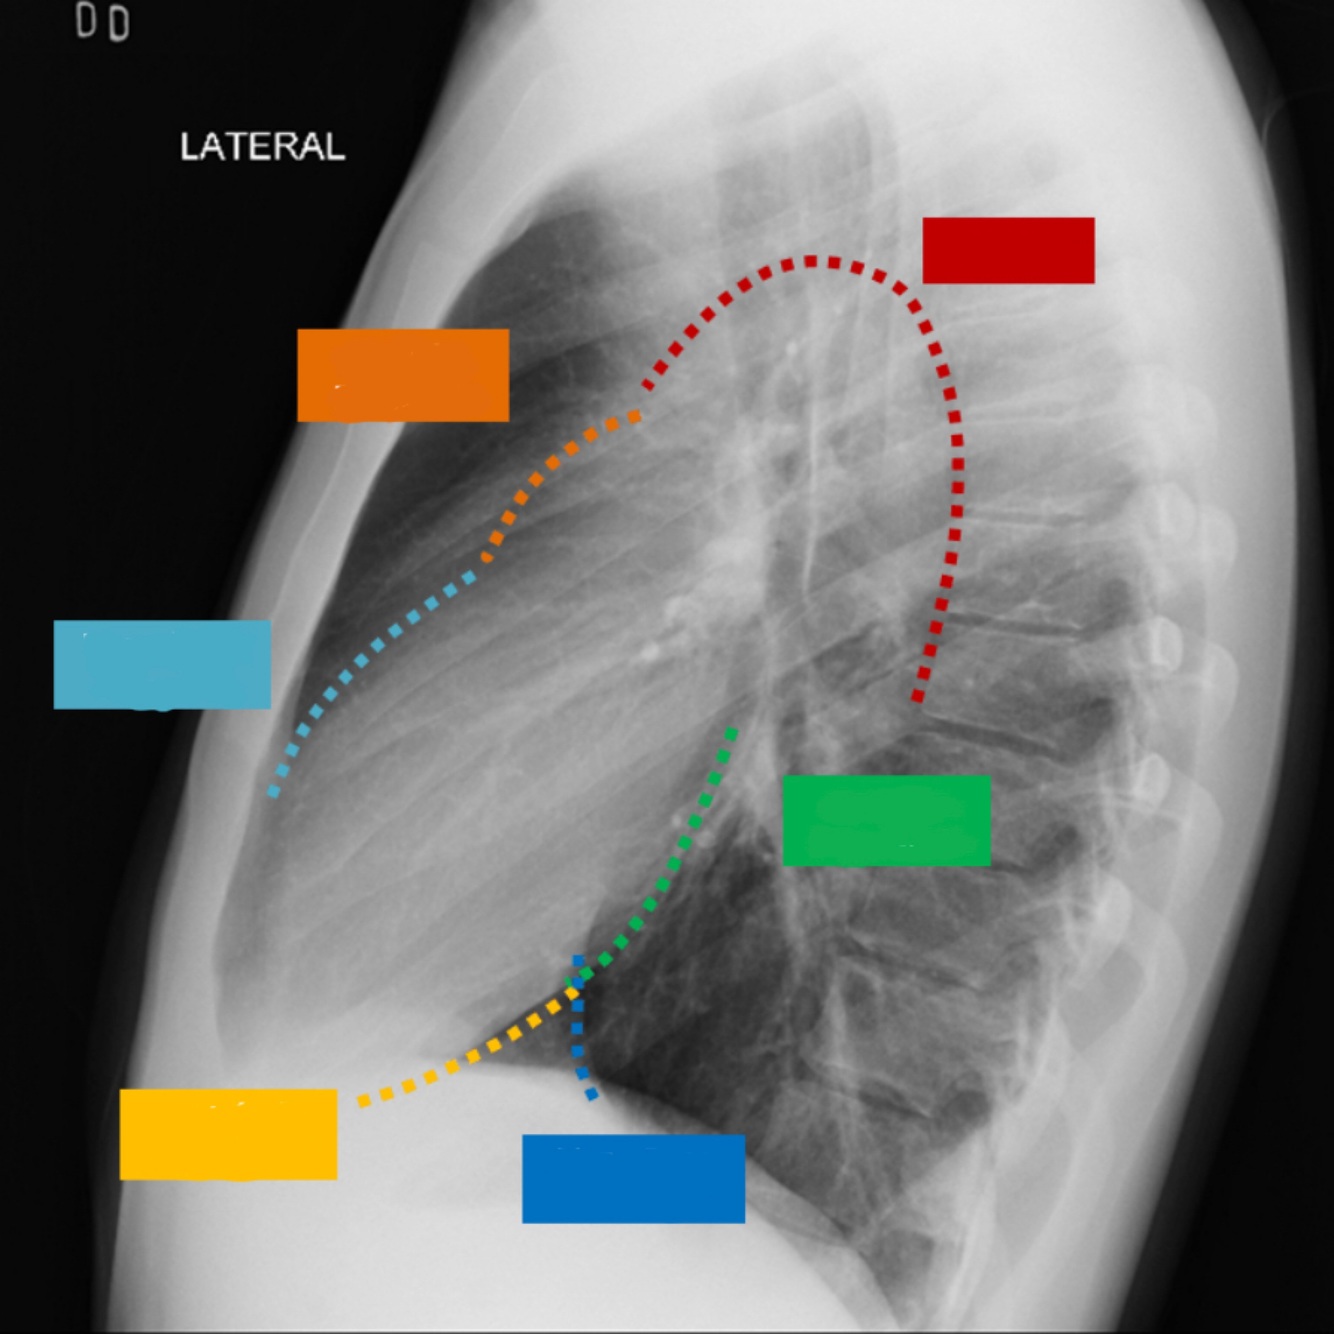

Que estructura anatómica esta en el numero 11

Traquea

41

Que estructura anatómica esta en el numero 13

Vasos supra aórticos

42

Que estructura anatómica esta en el numero 15

Espacio retro traqueal

43

Que estructura anatómica esta en el numero 9

Cayado aórtico

44

Que estructura anatómica esta en el numero 14

Espacio aéreo retro-esternal

45

Que estructura anatómica esta en el numero 19

Esternón

46

Que estructura anatómica esta en el numero 18

S.Cardiofrenico